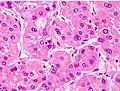

Microscopically, the four architectural and cytological types (patterns) of hepatocellular carcinoma are: fibrolamellar, pseudoglandular (adenoid), pleomorphic (giant cell), and clear cell. In well-differentiated forms, tumor cells resemble hepatocytes, form trabeculae, cords, and nests, and may contain bile pigment in the cytoplasm. In poorly differentiated forms, malignant epithelial cells are discohesive, pleomorphic, anaplastic, and giant. The tumor has a scant stroma and central necrosis because of the poor vascularization.[41] A fifth form – lymphoepithelioma like hepatocellular carcinoma – has also been described.[42][43]

Well-differentiated HCC

Moderately differentiated HCC.

Poorly differentiated HCC